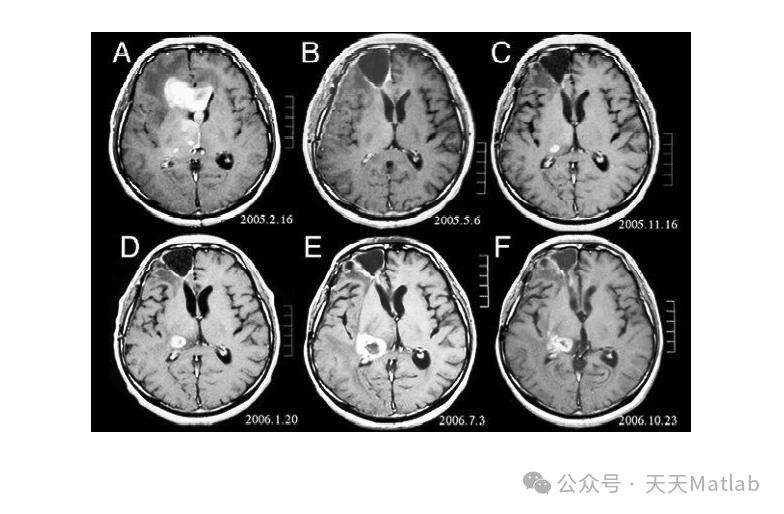

医学影像数据集则选用了公开的 MICCAI(Medical Image Computing and Computer-Assisted Intervention)脑部 MRI(Magnetic Resonance Imaging)图像数据集 。脑部 MRI 图像对于医学诊断具有重要意义,准确分割脑部组织如灰质、白质和脑脊液,能够为医生提供关键的诊断信息 。利用该数据集进行实验,可以检验算法在医学领域的应用潜力和分割精度 。

通过实验,我们得到了优化前后 PCNN 算法的分割结果图像,以及各项评价指标的数据 。从分割结果图像来看,传统 PCNN 算法在某些复杂场景下,如自然场景中物体边界模糊、医学影像中组织对比度较低以及工业检测图像中噪声干扰较大的情况下,分割结果存在较多的误分割和漏分割现象 。例如,在自然场景图像中,传统 PCNN 算法可能会将一些与背景颜色相近的物体部分误判为背景,导致物体分割不完整;在脑部 MRI 图像中,对于灰质和白质之间边界模糊的区域,传统 PCNN 算法容易出现分割不准确的情况;在工业检测图像中,噪声会干扰传统 PCNN 算法的分割结果,使得缺陷区域的分割出现偏差 。

相比之下,经过 NSGAII 优化后的 PCNN 算法在分割效果上有了显著提升 。在自然场景图像中,优化后的算法能够更准确地识别物体的边界,将物体从复杂的背景中完整地分割出来;在脑部 MRI 图像中,对于灰质、白质和脑脊液的分割更加精确,能够清晰地区分不同组织之间的边界;在工业检测图像中,优化后的算法对噪声具有更强的鲁棒性,能够准确地分割出产品表面的缺陷区域 。